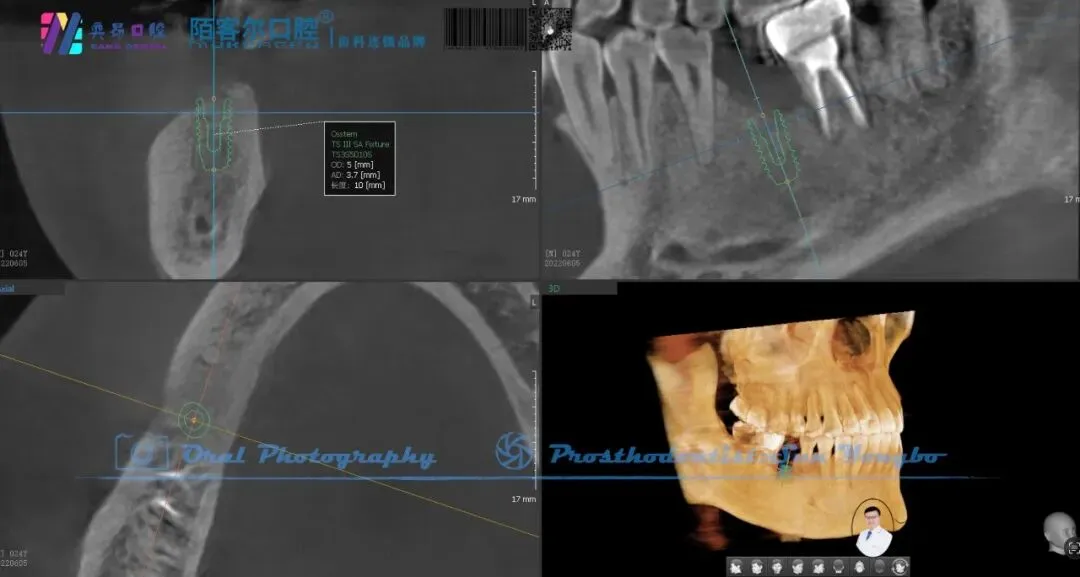

>【深圳牙医-孙永波】病例16丨右下后牙单颗缺失种植修复

【深圳牙医-孙永波】病例16丨右下后牙单颗缺失种植修复